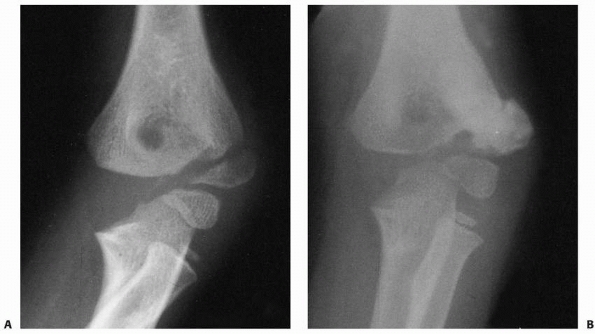

![]() |

FIGURE 15-27 A,B. Fracture of the capitellum in a 14-year-old boy. C,D. After open reduction and fixation with two small cannulated screws through a lateral approach.

|

if an anatomic reduction can be achieved with a minimum of open

manipulation or dissection, then we prefer to reattach it with two

small cannulated screws inserted from posterior to anterior through a

lateral approach. Enough bone must be present in the capitellar

fragment to engage the screw threads, and if possible, countersink the

heads of the screws (see Fig. 15-27). If the